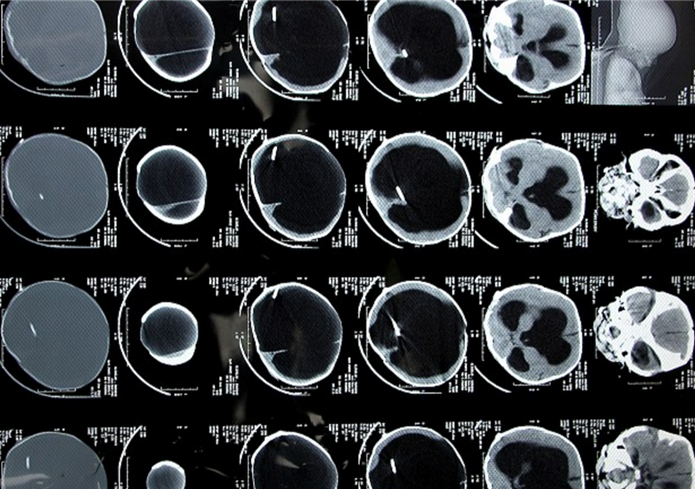

帕拉巴哈和丈夫?yàn)榱酥委熈_亞爾的疾病已經(jīng)花費(fèi)了2000英鎊(約1.75萬(wàn)元人民幣),但目前看來(lái),羅亞爾的病情并沒(méi)有明顯好轉(zhuǎn)。醫(yī)生目前的治療方案是通過(guò)分流將羅亞爾腦中的積液引入血液,以減輕羅亞爾腦部壓力。

帕拉巴哈的丈夫拉金德拉是一名勞工,每月的收入只有50英鎊(約438元人民幣)??紤]到羅亞爾的病情以及夫婦二人的經(jīng)濟(jì)狀況,醫(yī)院本周免費(fèi)為羅亞爾進(jìn)行了新一輪手術(shù)。該醫(yī)院神經(jīng)外科的副主任錢德拉表示,羅亞爾之前在別家醫(yī)院植入的分流器已經(jīng)停止工作,在這次的手術(shù)中,醫(yī)生在羅亞爾腦部的另一側(cè)植入了新的分流器,目前,羅亞爾的情況正在一天天好轉(zhuǎn)。

錢德拉說(shuō):“這種疾病的死亡率極高,患者的身體和腦部發(fā)育都異于常人。如果沒(méi)有及早發(fā)現(xiàn)、及早治療,嬰兒死亡的可能性將更大?!?/p>